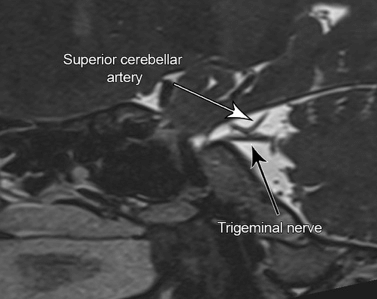

The most common cause of idiopathic Trigeminal Neuralgia is a ‘neurovascular conflict’. The intracranial portion of the Trigeminal Nerve lies in a space called the Pre-pontine Cistern. The Superior Cerebellar Artery normally runs close to but not touching the nerve. Most patients of Trigeminal Neuralgia have an anomaly where the artery touches this nerve and the constant pulsation causes nerve damage in the form of Demyelination – not different from damage to the insulation on an electric wire if it constantly rubs against a wall. This nerve damage causes hypersensitivity of the nerve and causes the pain. The conflict may be most commonly due to the artery mentioned above but often other vascular structures such as a vein or other arteries may cause the same. While this is the commonest cause, other causes include tumors in the area of the Trigeminal Nerve and rarely Multiple Sclerosis.

Evaluation is by a detailed history and examination specifically regarding a trigger point or the starting point of the pain in the face. This is important for deciding the treatment of the patient. A high resolution MRI of the brain with cisternography (CISS-3D/FIESTA sequences) in coronal, axial and sagittal planes is required for 2 reasons – to rule out a tumor (meningioma, epidermoid), or aneurysm, or Multiple Sclerosis; and to look for the vascular loop touching the nerve.